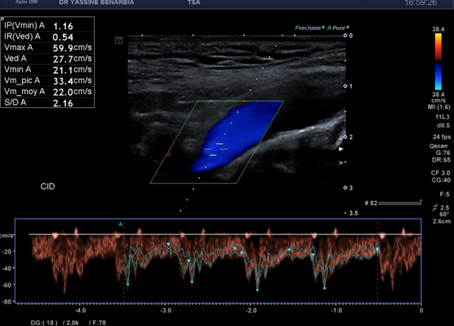

Du côté droit, l'examen met en évidence une dissection du tronc brachiocéphalique (TABC) avec présence d'un faux chenal circulant. Le flap intimal est clairement visible en mode B, séparant le vrai chenal du faux chenal. Au Doppler couleur, on observe un double flux avec des vélocités différenciées : le vrai chenal présente un flux rapide (codé en bleu qui s’éloigne de la sonde) tandis que le faux chenal montre un flux plus lent (codé en rouge qui se rapproche de la sonde).

Cette dissection s'étend à la carotide commune droite proximale. Le Doppler pulsé dans le vrai chenal montre un spectre triphasique conservé avec une vélocité maximale de 108,0 cm/s (normale) et un index de résistivité de 0,84 confirmant l'absence de retentissement hémodynamique. L'artère sous-clavière droite et l’artère vertébrale restent perméables avec des flux normaux au doppler.